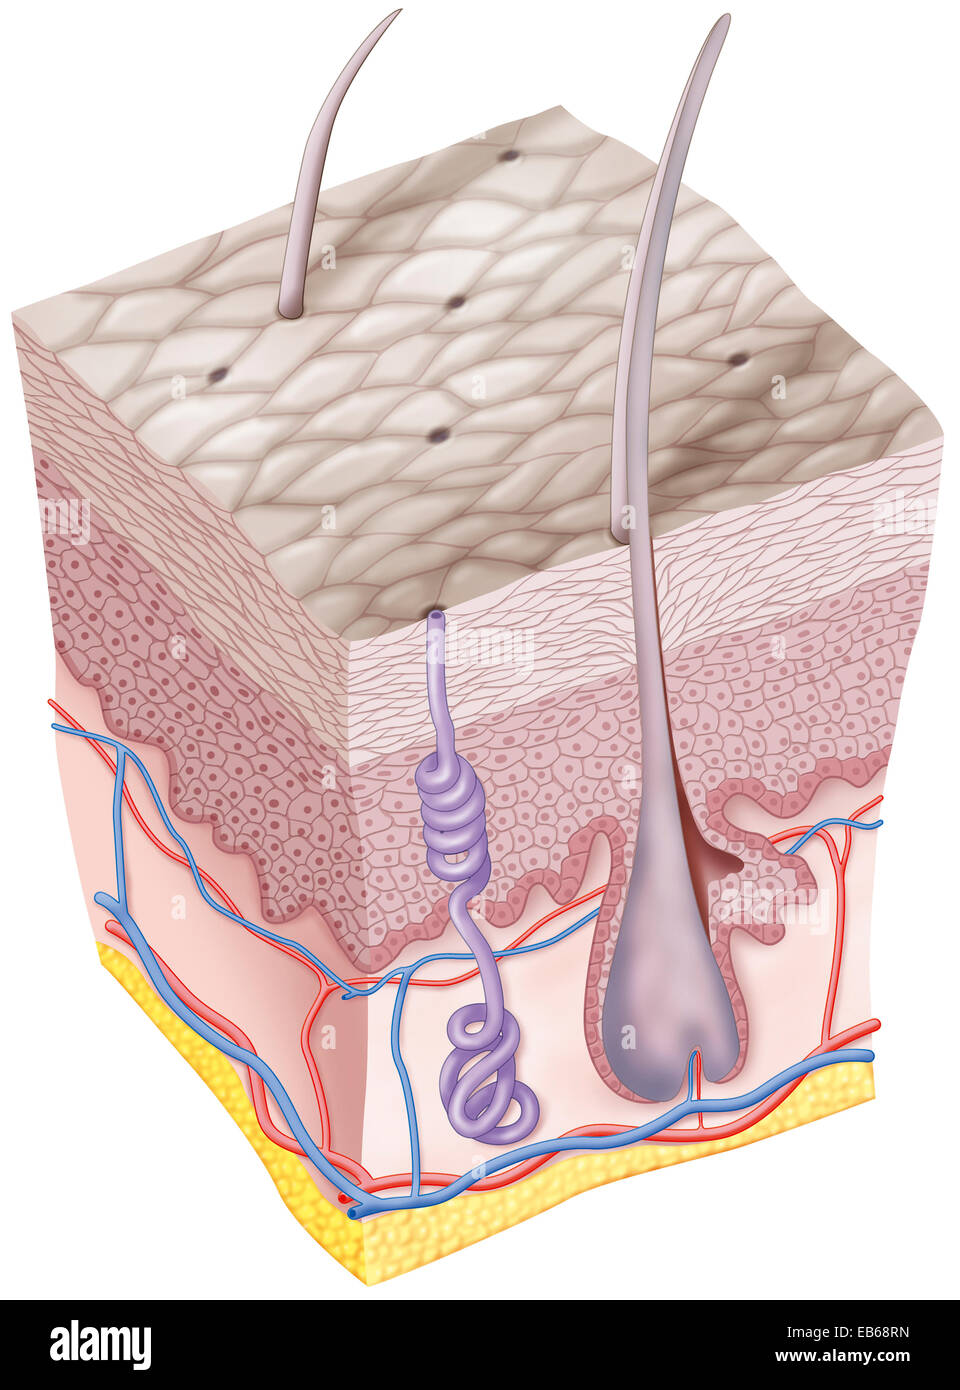

SCAR DRAWING Stock Photohttps://www.alamy.com/image-license-details/?v=1https://www.alamy.com/stock-photo-scar-drawing-75741327.html

SCAR DRAWING Stock Photohttps://www.alamy.com/image-license-details/?v=1https://www.alamy.com/stock-photo-scar-drawing-75741327.htmlRMEB68RB–SCAR DRAWING